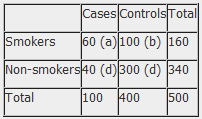

The results of a case-control study can be presented in a 2x2 table as follow:

The odds ratio is a measure of the odds of disease in the exposed compared to the odds of disease in the unexposed (controls) and is calculated as:

Example: Calculation of the OR from a hypothetical case-control study of smoking and cancer of the pancreas among 100 cases and 400 controls. Table 1. Hypothetical case-control study of smoking and cancer of the pancreas.

OR = 60 x 300 100 x 40 OR = 4.5 The OR calculated from the hypothetical data in table 1 estimates that smokers are 4.5 times more likely to develop cancer of the pancreas than non-smokers. NB: The odds ratio of smoking and cancer of the pancreas has been performed without adjusting for potential confounders. Further analysis of the data would involve stratifying by levels of potential confounders such as age. The 2x2 table can then be extended to allow for stratum specific rates of the confounding variable(s) to be calculated and, where appropriate, an overall summary measure, adjusted for the effects of confounding, and a statistical test of significance can also be calculated. In addition, confidence intervals for the odds ratio would also be presented.